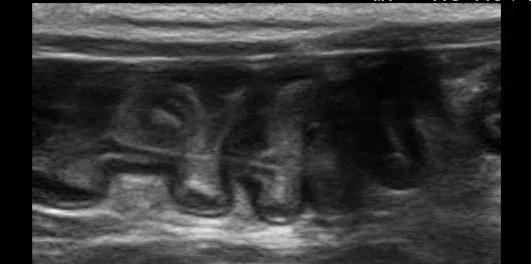

2025/09/24 ひもを丸呑み!?〜長いひもが引き起こす、ちょっと怖い誤食の話〜 ⚠️ ご注意くださいこの投稿には、手術中の写真や臓器・血液を含む画像が掲載されています。医療的な内容にご関心のある方向けの投稿となっておりますので、出血や臓器の画像が苦手な方は、閲覧をお控えください。 「ひもや糸で遊ぶの […] MORE

2025/09/18 異物などの誤食・消化管の閉塞について ペットが異物を口にしてしまうケースは、実はとてもよくあることです。中には「まさか、こんなものを食べるなんて…」というご相談も多く、飼い主さまにとっても予想外の出来事に戸惑われることが少なくありません。特に、若くて食欲旺盛 […] MORE